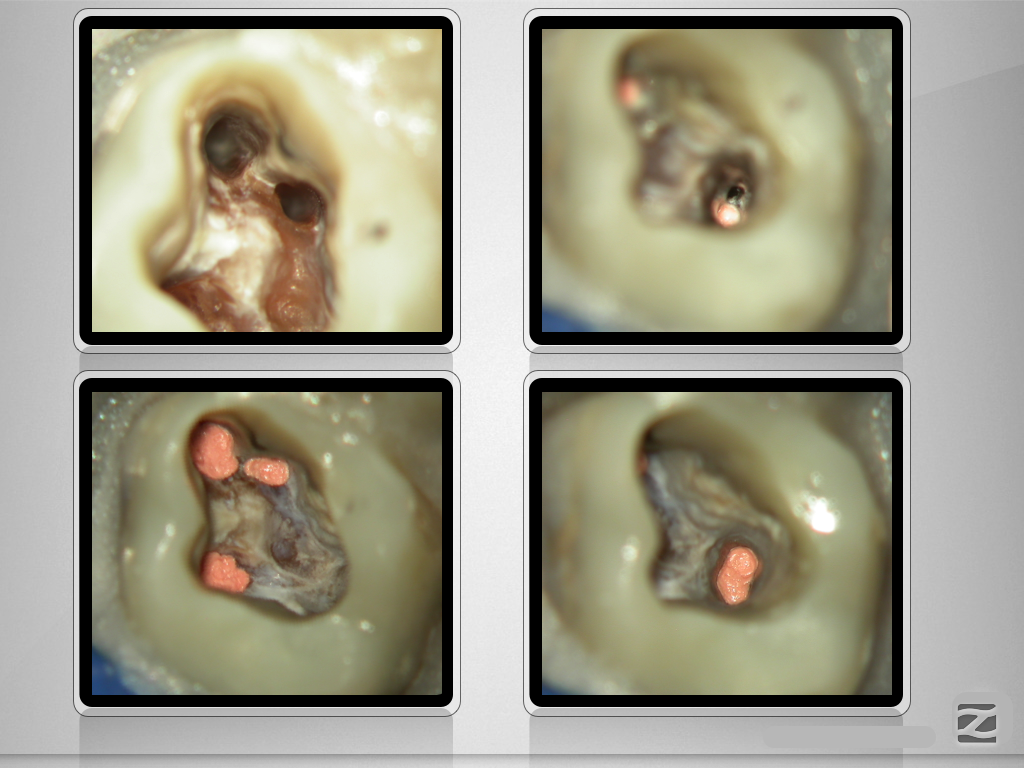

26D.003

Unerwartetes